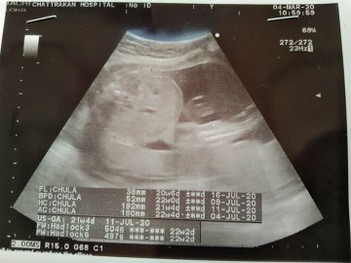

แบบนี้ น้ำหนัก ลูกเราเท่าไหร่ค่ะ พอดีดูไม่เป็นค่ะ

504g 497g จ้าจะครึ่งโลแล้วค่ะ